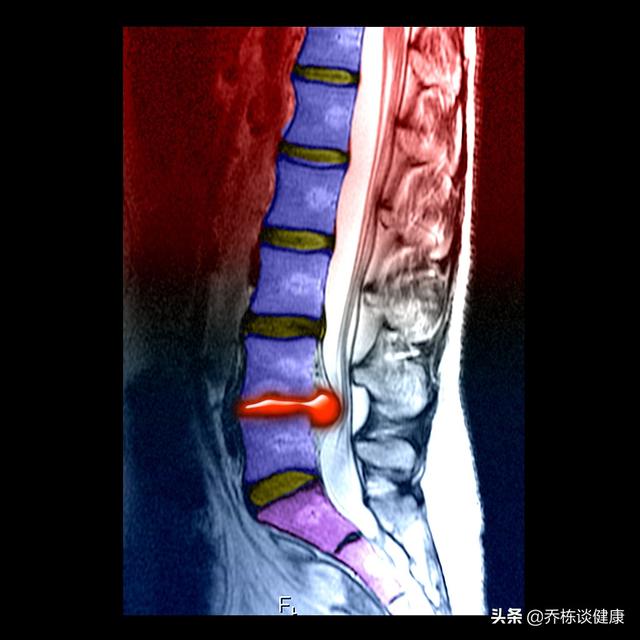

lumbale Spinalkanalstenose

Die lumbale Spinalkanalstenose, die eigentlich einen geringeren Durchmesser des Wirbelkanals beschreibt, kann durch eine ganze Reihe von Faktoren ausgelöst werden, z. B. durch einen von Geburt an verengten Wirbelkanal oder durch Osteophyten oder Tumore, und am häufigsten sind es natürlich die lumbalen Bandscheibenvorfälle, die sich ausbreiten und zu einer Spinalkanalstenose führen, und im Kern geht es dabei um die Symptome.

Offensichtlich handelt es sich hier um eine lumbale Spinalkanalstenose, und auch hier werden die MRT-Ergebnisse gelesen.

Die lumbale Spinalkanalstenose ist das Phänomen, die lumbale Spinalkanalstenose ist die Krankheit. Was sind die Symptome der lumbalen Spinalkanalstenose? Das typischste Symptom ist die Claudicatio intermittens, d. h., je mehr man geht, desto mehr schmerzen die Beine und desto schwächer werden sie, und man muss sie entlasten, indem man in die Hocke geht oder sich bückt, und dann weitergeht. Beachten Sie, dass eine lumbale Spinalkanalstenose keine Beinschmerzen verursacht, während Beinschmerzen in der Regel bei einem lumbalen Bandscheibenvorfall auftreten. Der Unterschied zwischen den beiden ist einfach, machen Sie einen geraden Beinheben Test, lumbale Spinalkanalstenose kann getan werden, lumbalen Bandscheibenvorfall ist kategorisch nicht.